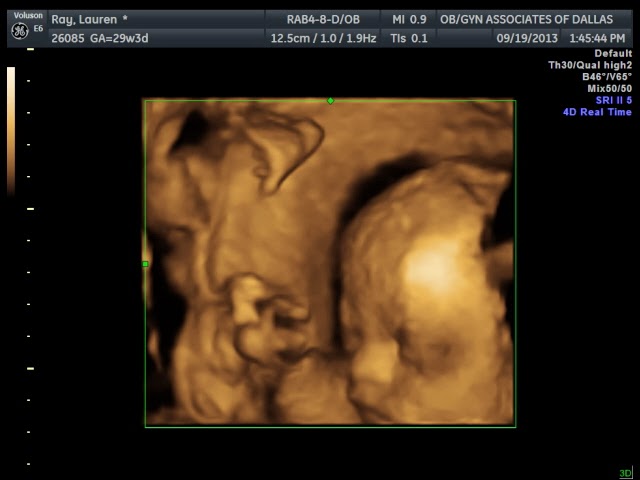

Now for the 4d Sono... She was NOT cooperative, but we didn't expect her to be. She decided today was yoga day, and had her feet and hands all the way up in front of her face. She weighs about 3.3 lbs and her heart rate was measuring 134bpm, which is great! We go back in 3 weeks for our next appointment and will do this again to see if we get some better pics. Here are a few from today...

profile

smile!

so in love already

sweet baby girl